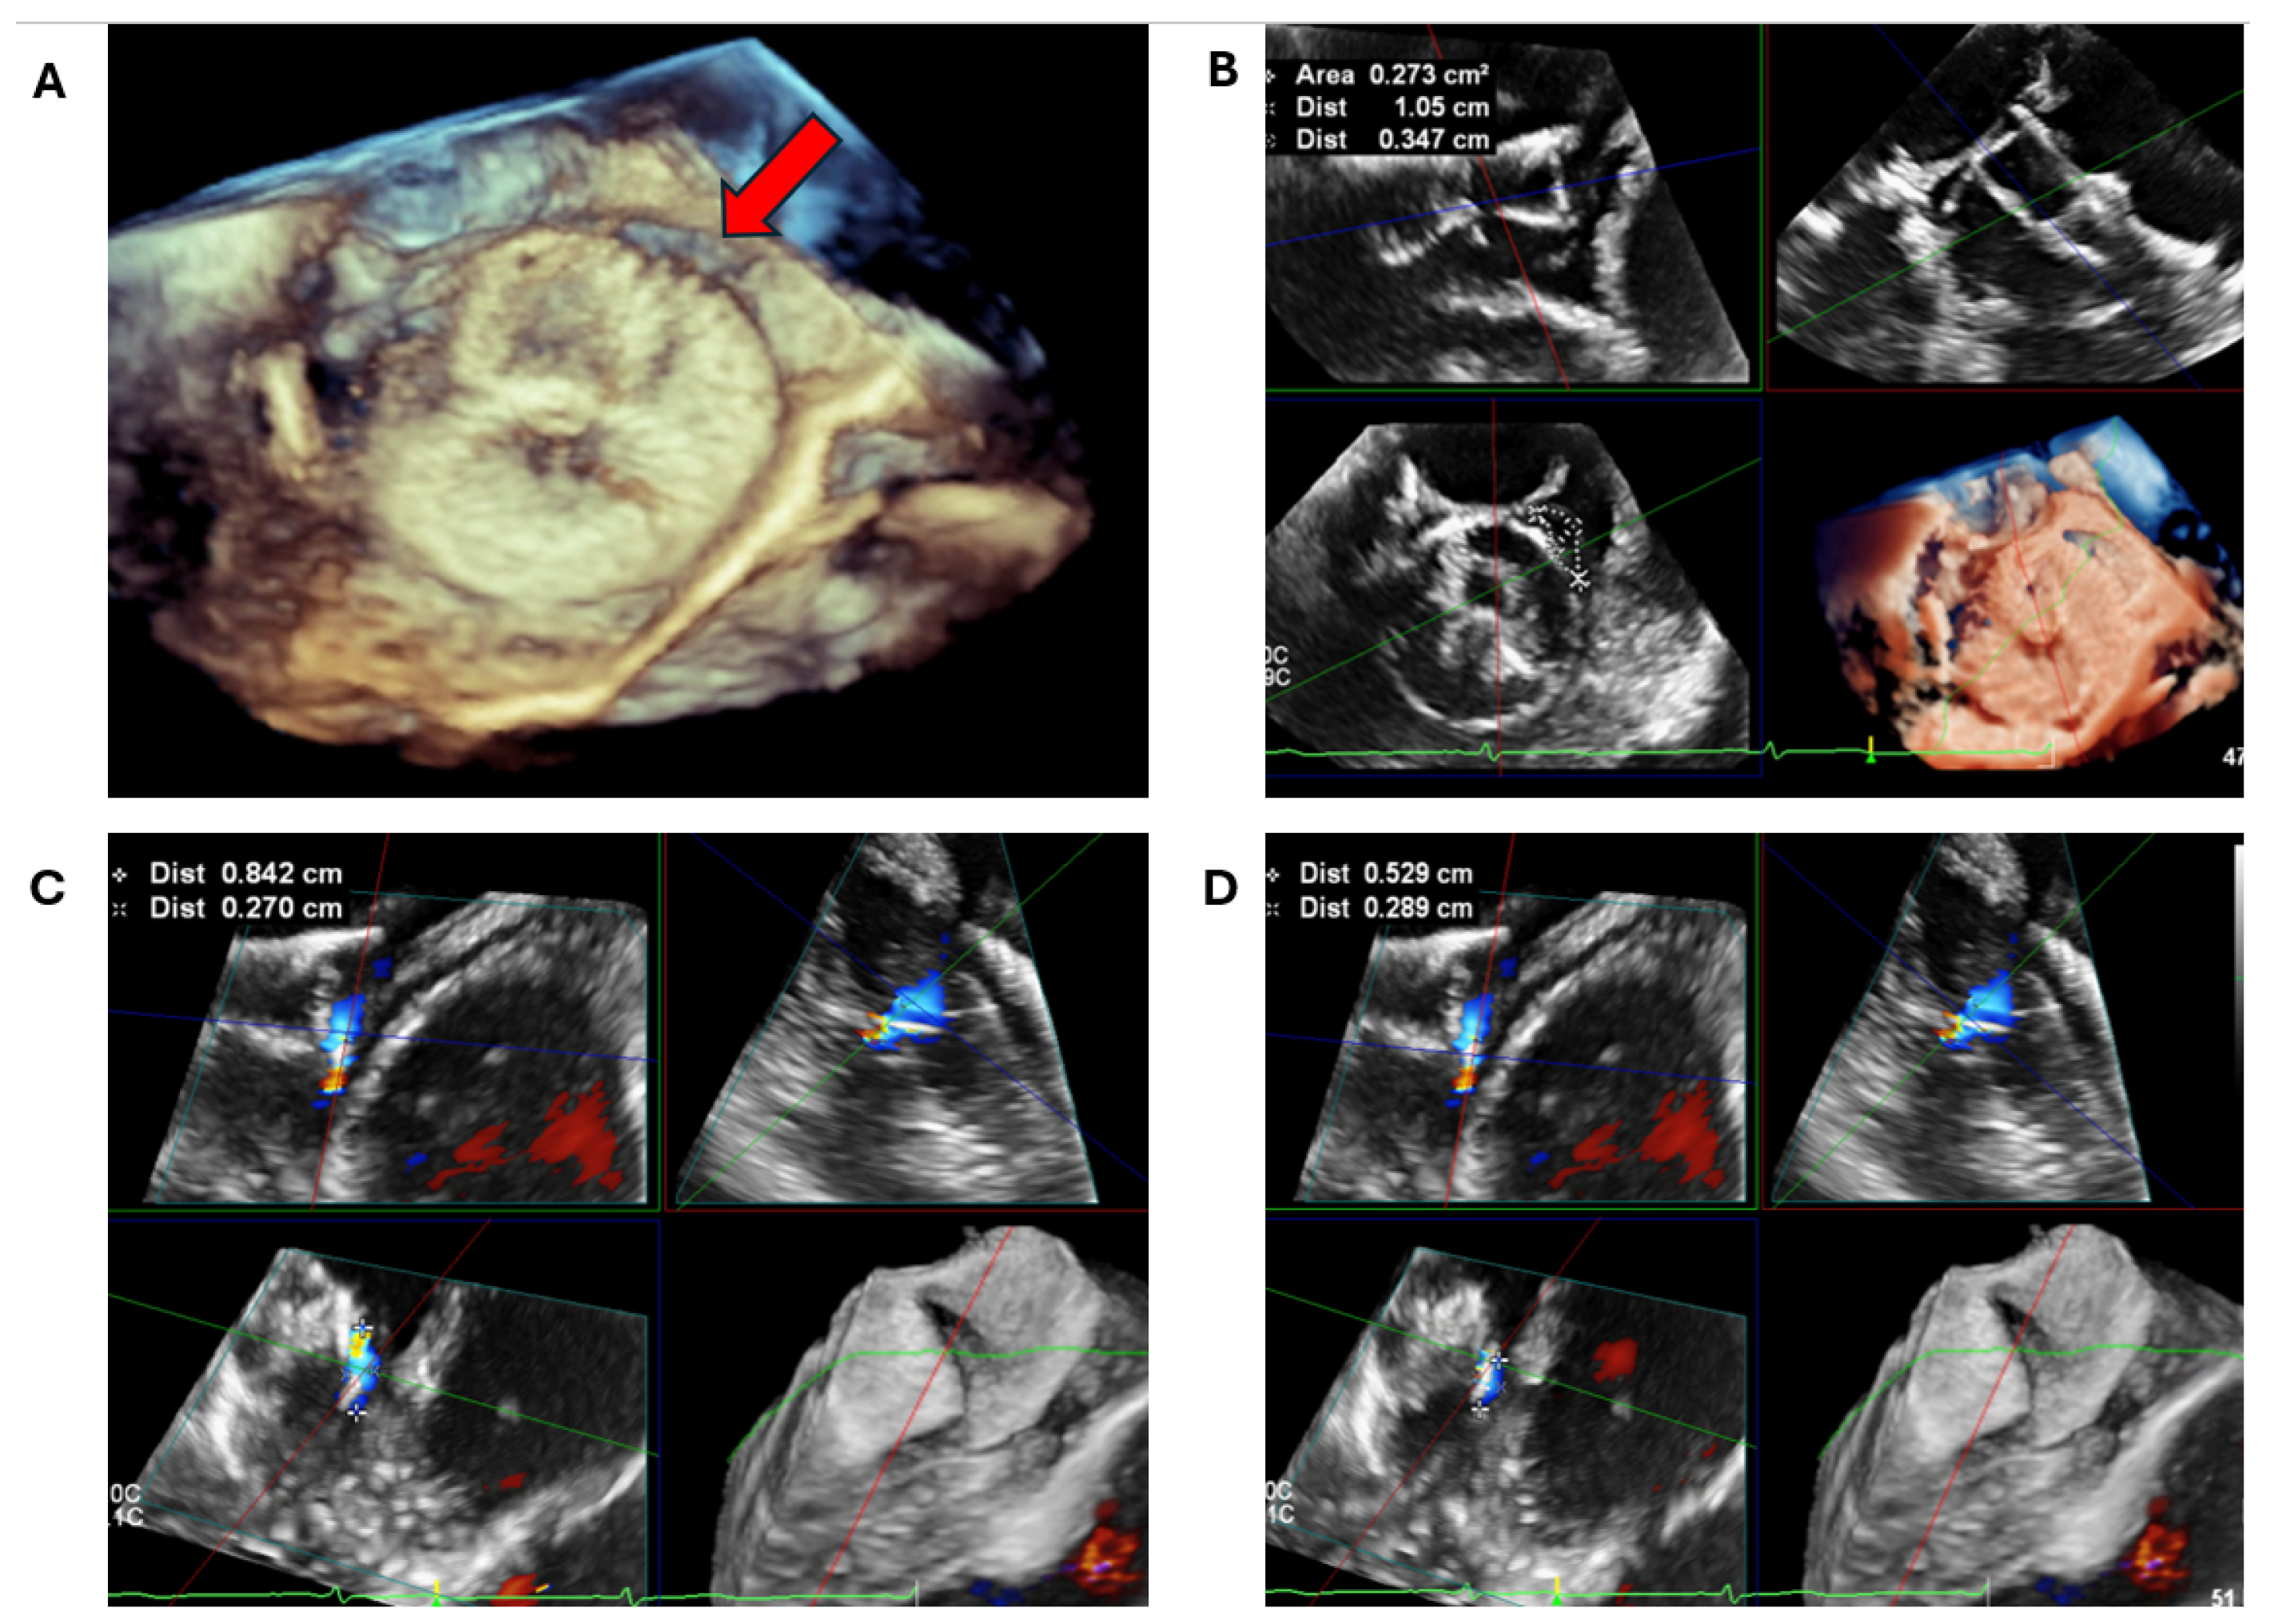

2.2.1. LAA Thrombus Assessment

2.2.2. LAA Measurements (Anatomy and Morphology)

2.2.3. Intra-Procedural TOE

3.2. Peri-Device Leaks

3.3. Device-Related Thrombus